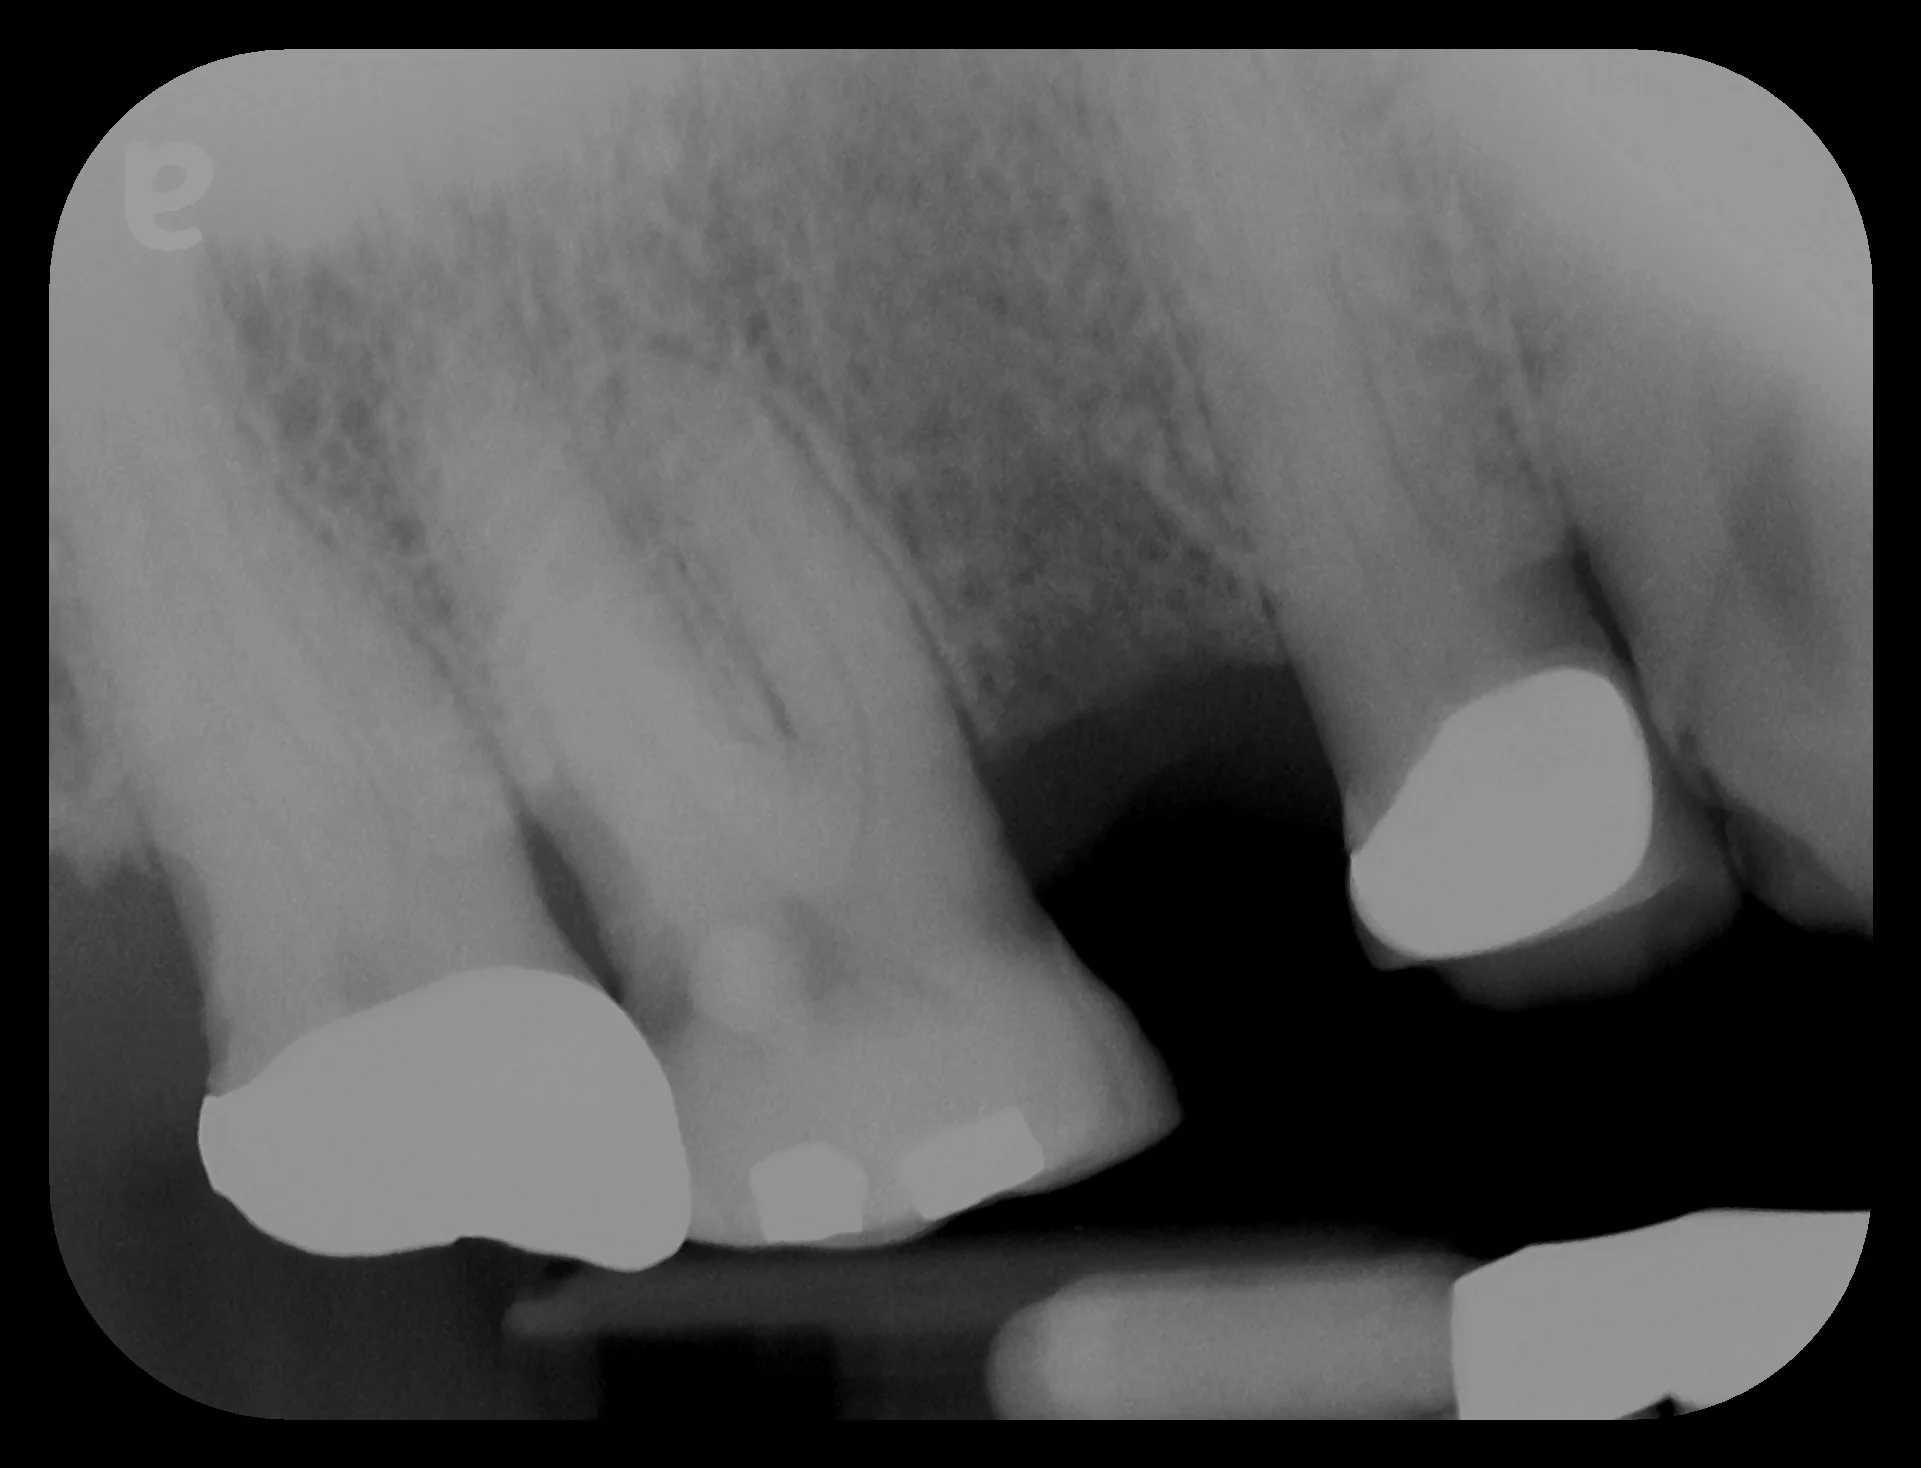

"Another doomed root canal."

Our patient had a root canal that eventually failed due to root fracture.  Another tale of extraction, bone graft and implant placement.  This case took approximately 5 months to complete.